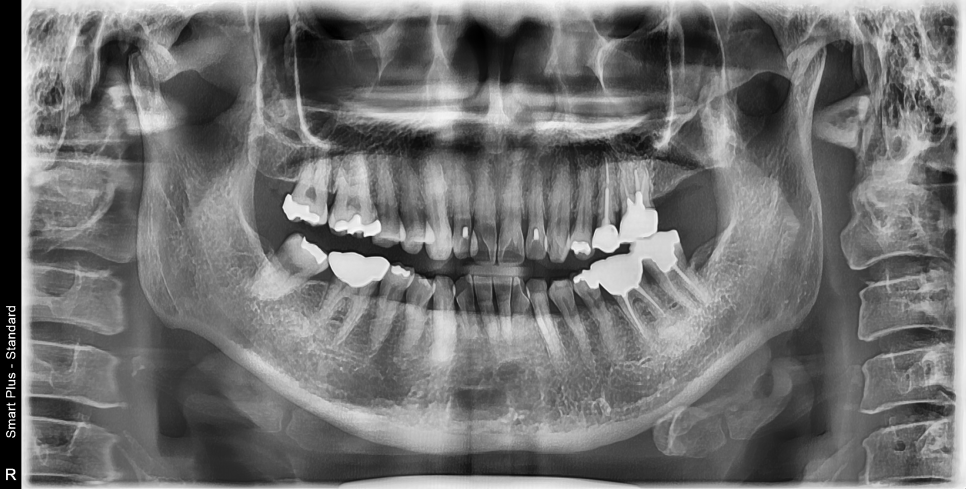

60대 중년여성 진단사진

이분 케이스는 앞니만 부분적으로 교정하시는 것은 한계가 있어서 지금 전체교정을 진행중에 있으십니다.